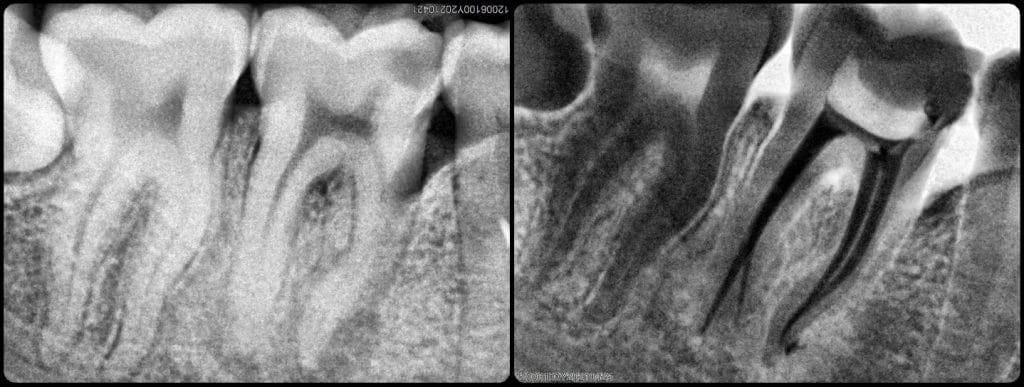

RCT for tooth No. 46 with apical split in the distal root.

Preopretaive x-ray show a wide distal canal Then the split.